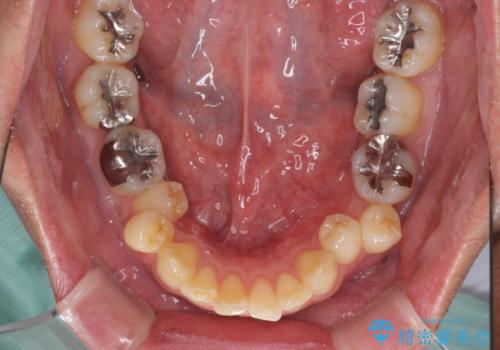

- 外に飛び出した側方の歯と、前歯のデコボコを気にして来院された患者様です。

IPR(歯と歯の間を削る)によってデコボコが解消するように設計し、インビザラインにより治療を行うこととしました。

治療途中で1年半以上通院されない時期があったため、後戻りが生じたことで治療期間が長くなってしまいました。

親知らずを抜去したことで、下顎のデコボコがきれいに解消されました。